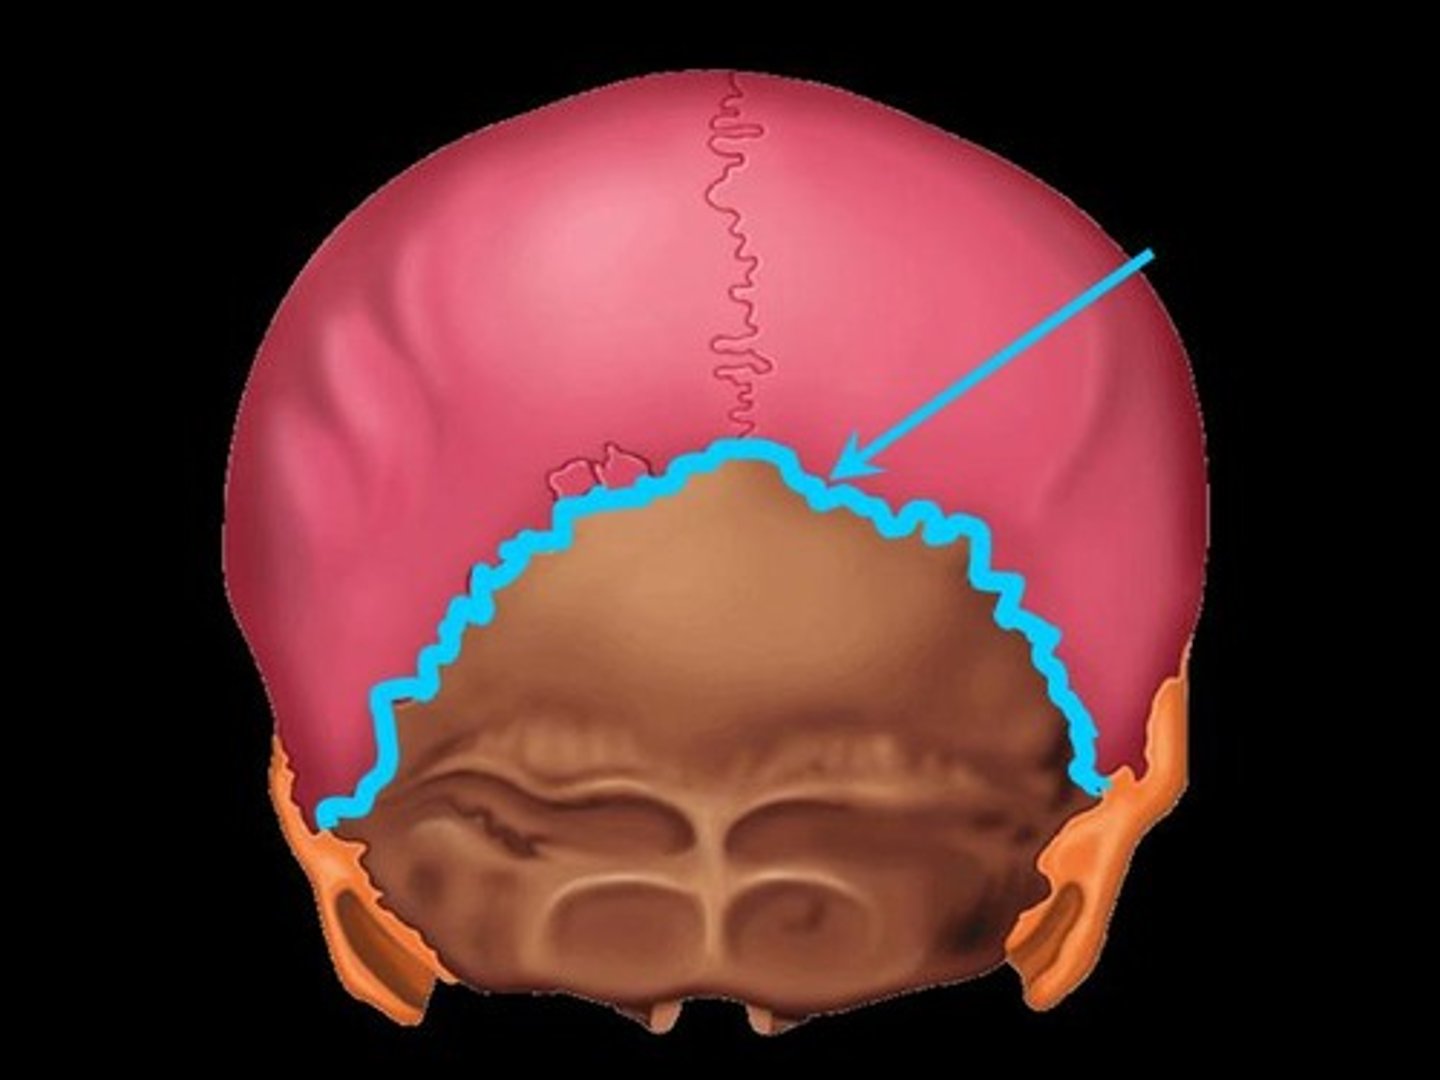

lambdoid suture